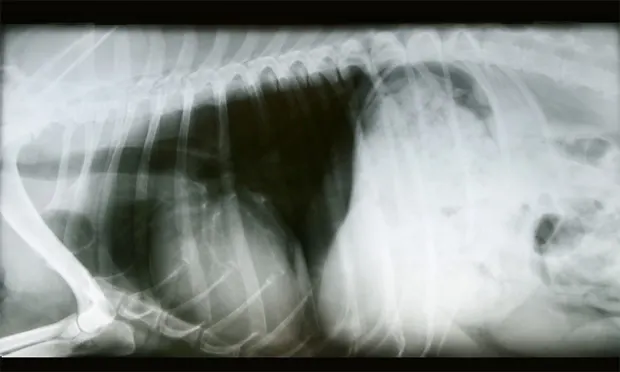

A radiograph shows a lateral view of a dog's thorax, highlighting the ribcage, heart, and lungs. The image reveals potential abnormalities in the cardiac silhouette and lung fields, indicating areas of interest for further evaluation.

Using the VHS to interpret thoracic radiographs can allow you to evaluate any size breed and make a prompt diagnosis in your clinic. Developed by Dr. James W. Buchanan and Dr. Jōrg Bücheler at the University of Pennsylvania, finding the VHS lets you determine whether your patient has an enlarged heart.2

2. Using calipers, measure the longest axis of the cardiac silhouette from the carina of the mainstem bronchus to the apex (Long Axis “L”).

3. Transfer this long axis measurement to the vertebrae, starting from the cranial edge of T4. Count the number of vertebrae within the caliper measurement.

4. Using calipers, measure the short axis at the widest part of the cardiac silhouette (Short Axis “S”). This measurement should be taken perpendicular to the long axis.

5. Transfer this short axis measurement to the vertebrae, starting from the cranial edge of T4. Count the number of vertebrae within the caliper measurement.

6. Add the two numbers: VHS = L + S. A normal VHS for most dogs is between 8.7 and 10.7.